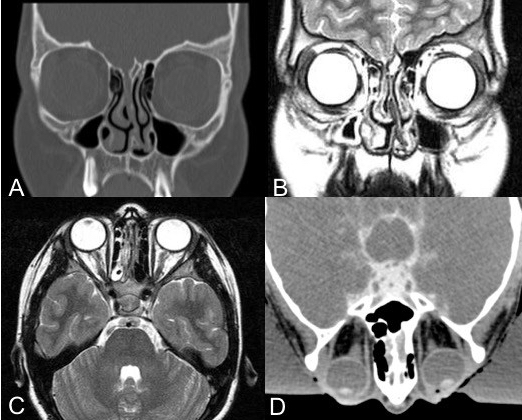

diagnostic radiologique

le bilan radiologique peut rester négatif ou douteux, c’est l’exploration chirurgicale qui est le critère diagnostique de référence.